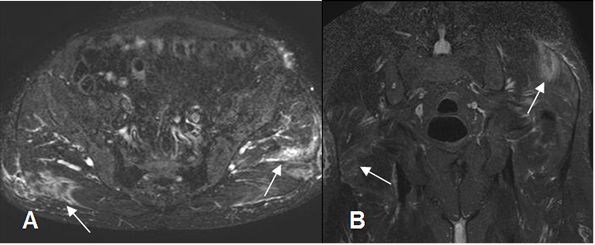

Fig 26 B. DOMS.

A: RM axial y B: RM coronal en STIR. Edema muscular en el glúteo mayor derecho y glúteo mediano izquierdo secundario a DOMS, luego de una practica deportiva extrema.